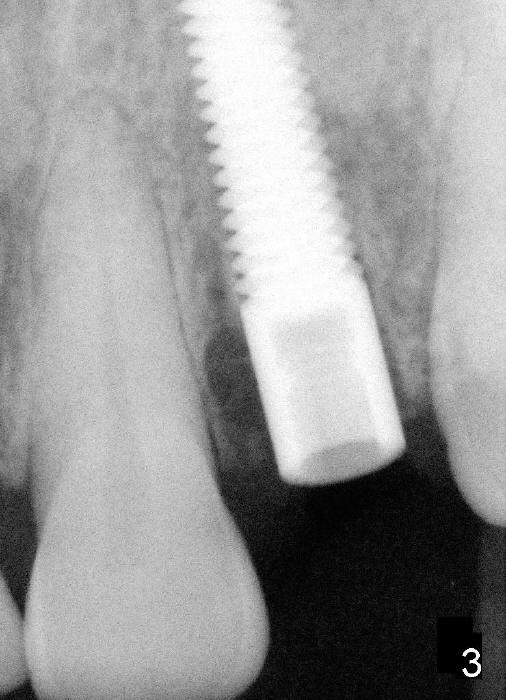

Fig.2: A gutta percha inserted to the buccal fistula (Fig.1 >) shows a mesial defect ( <). *: periapical radiolucency. Fig.3. Immediately post implantation (4x20 mm). Fig.11: Four months postop. Crest bone appears to have mild resorption (arrow).